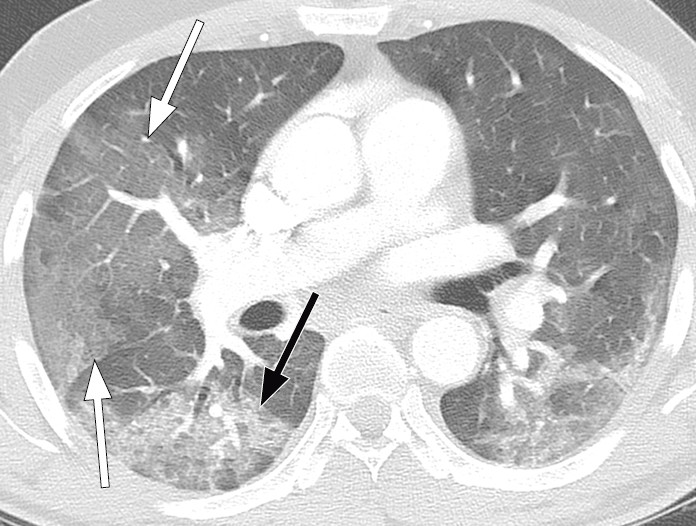

Typiske CT-funn varierer med symptomvarighet og kan deles i tre stadier: en tidlig fase, en intermediær fase som strekker seg fra 3–5 dager etter symptomdebut, og en senfase. Det er ikke alltid funn på CT de første dagene etter symptomdebut. I et materiale med symptomatiske, men uspesifiserte pasienter hadde 56 % normale funn på CT innen to dager etter symptomdebut (12), avtakende til 9 % 3–5 dager etter symptomdebut og 4 % 6–12 dager etter symptomdebut. Funnhyppighet varierer med sykdommens alvorlighetsgrad. Ved første gangs bildediagnostikk var det normale funn hos 18 % i en gruppe pasienter med ikke alvorlig sykdom, men hos bare 3 % av pasienter med alvorlig sykdom (15). Typiske CT-funn er multiple, bilaterale mattglassfortetninger med perifer distribusjon, hyppigst lokalisert i underlappene. I intermediær fase er det økende innslag av konsolidering (tette infiltrater) og affeksjon av flere lapper samt økt septering med brosteinsmønster (crazy paving) som tegn på interstitiell affeksjon. I senfasen er det økende total utbredelse, men mattglassfortetninger og konsolidering er fremdeles dominerende funn (12, 16). Figur 4, figur 5 og figur 6 viser typiske funn på CT i ulike faser av covid-19.

Ved alvorlig sykdomsforløp kan det påvises distorsjon av lungearkitekturen, traksjonsbronkiektasier, forstørrede lymfeknuter og pleuravæske. Dette er funn som ikke er spesifikke for covid-19 (17).